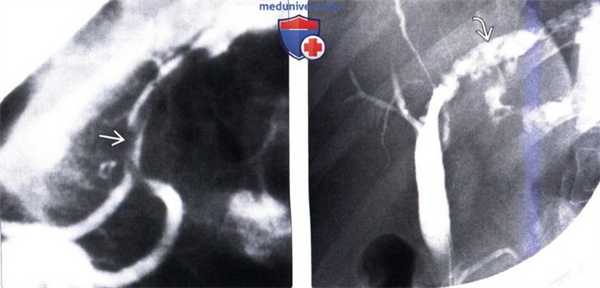

(Слева) На рентгенограмме (ЭРХПГ) визуализируется аскарида в главном панкреатическом протоке, поражение которого происходит значительно реже по сравнению с желчными протоками, скорее всего, из-за его относительно небольшого диаметра. Воспаление поджелудочной железы может быть обусловлено паразитарной инвазией панкреатического протока или желчных протоков.

(Справа) На рентгенограмме (ЭРХПГ) определяется расширение левого печеночного протока с наличием множественных дефектов наполнения, обусловленных трематодами. Вытянутая форма дефектов больше характерна для трематод в просвете внутрипеченочного протока, чем для конкрементов.

• ЭРХПГ: дефекты наполнения линейной, эллиптической или округлой формы в расширенных желчных протоках или панкреатическом протоке